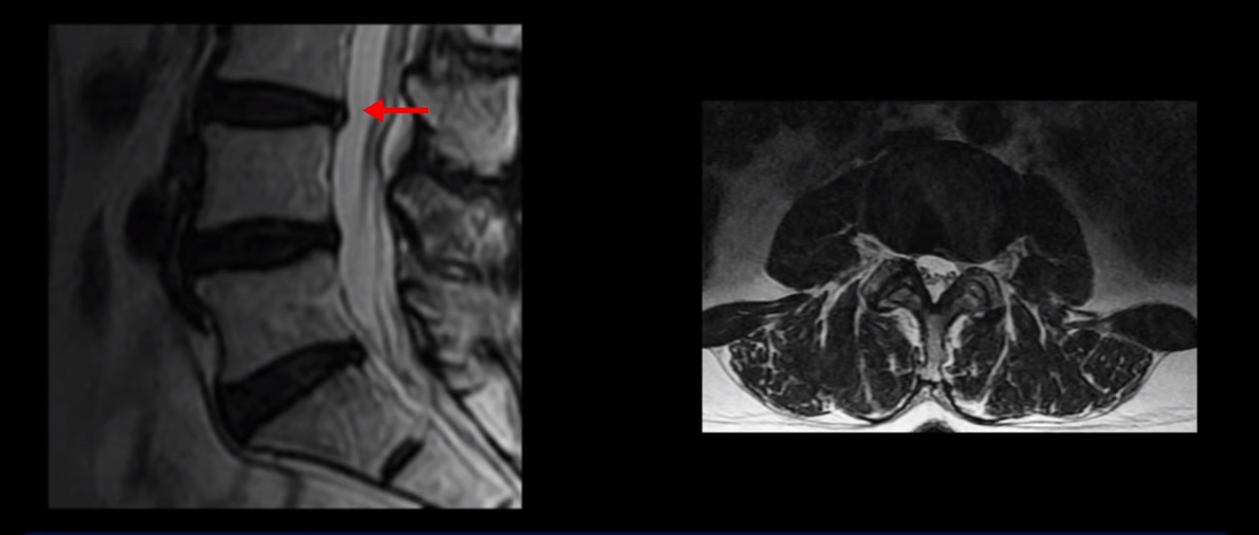

우선 제가 MRI를 보면서 설명드린 후 어떻게 이런 환자분이 즉 수술 후에도 마비가 풀리지 않고 방사통도 좋아지지 않고 오히려 악화되는 환자분이 비수술 치료로 회복될 수 있는지 설명 드리겠습니다.

이분 MRI를 보시면 허리 세 마디가 퇴행은 있으나

척추관도 3번 4번

4번 5번

5번 1번

전부 다 충분히 넓고 왼쪽 다리 쪽으로 신경이 나가는 추간공도 전부 다 충분히 넓은 상태입니다.

신경이 눌려 보이지 않는 겁니다. 그러니까 수술 후 MRI를 보고 모든 병원이 전부 다 ‘수술은 잘돼 있다’, ‘아무것도 해줄 게 없다’ 그냥 기다리라고만 얘기했다고 합니다. 신경외과, 정형외과, 재활의학과가 서로 다른 과로 전과시키면서 다들 아무것도 해줄 게 없다고 하니 희망을 잃은 상태였다고 했습니다.